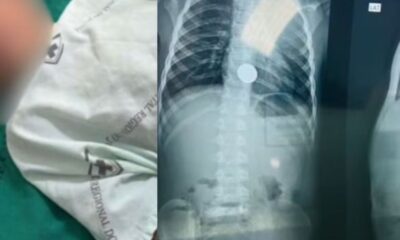

Um menino de cinco anos precisou ser transferido do Hospital Dr. Abel Pinheiro Maciel Filho, em Mâncio Lima, no interior do Acre, para o Hospital Regional...